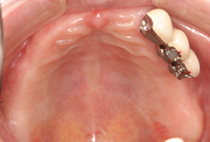

インプラント治療例 義歯機能不良による咀嚼障害

義歯機能不良による咀嚼障害です。

長期の義歯使用により顎の骨がかなりやせ、義歯が安定せず上手く噛めません。

インプラント支持による固定された歯列により何でも好きなものを食べれるようになりました。